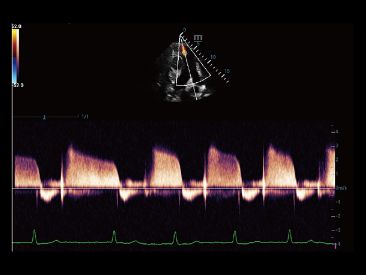

Assim como o n├Łvel de qualidade de imagem premium, o Resona 7 tamb├®m melhora as capacidades de investiga??o cl├Łnica com o revolucion├Īrio Fluxo V para avalia??o hemodin?mica vascular e a aquisi??o de plano mais inteligente do conjunto de dados 3D para diagn├│stico CNS fetal. Combinando a opera??o mais intuitiva baseada em gesto de multi-toques e todos os recursos cl├Łnicos essenciais, Resona 7 est├Ī realmente conduzindo novas ondas na inova??o de ultra-som.